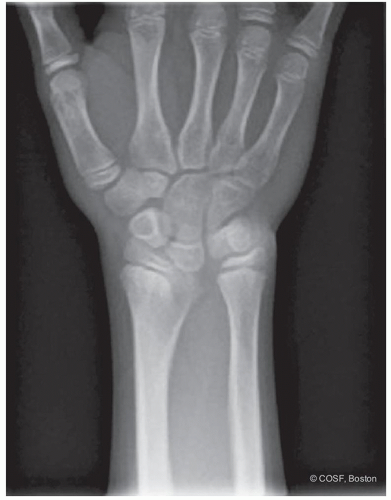

Lunate fossa deformity (Figure 15.1)

Volar and proximal carpal subluxation (Figure 15.2)

Distal radioulnar joint (DRUJ) incongruity secondary to distal radius deformity and ulna overgrowth (Figure 15.3)